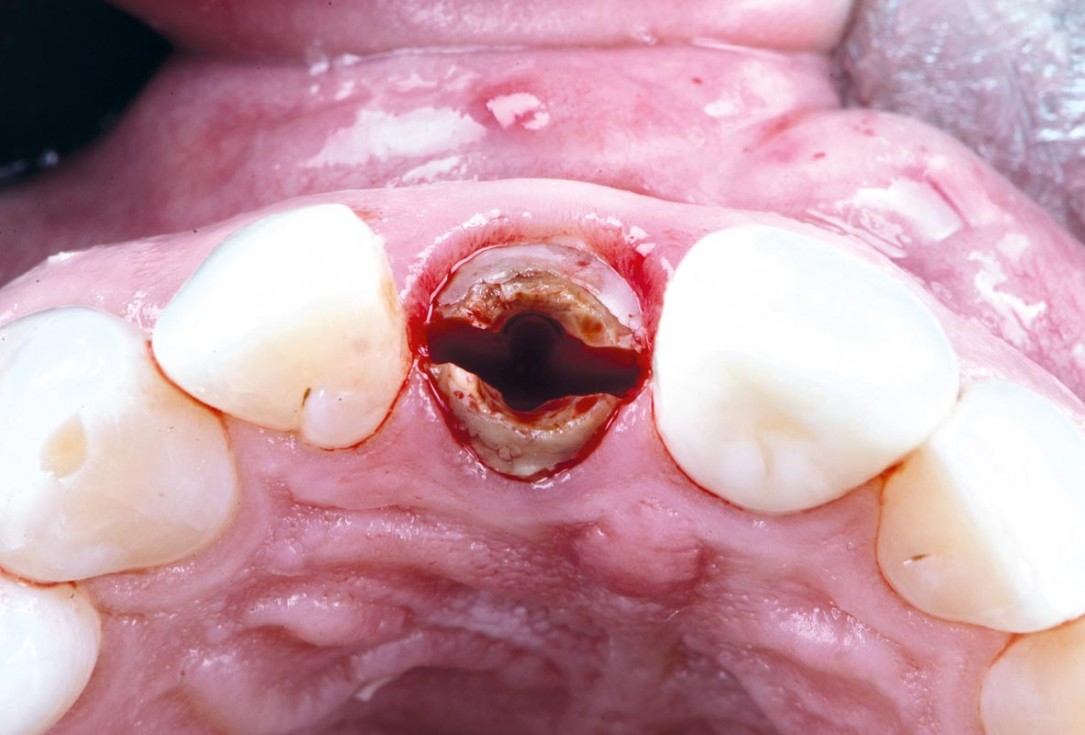

Initial clinical situation - Central incisors with dental destruction and periapical pathology